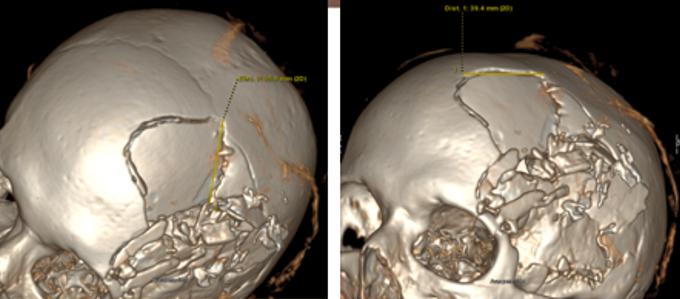

Une étude évalue les capacités des MERM à détecter des fractures au scanner basse dose

Des chercheurs australiens ont évalué l'aptitude des MERM à identifier des fractures sur un fantôme pédiatrique en scanner basse dose. Les participants ont bien détectées celles du crâne et du tibia, moins bien ...